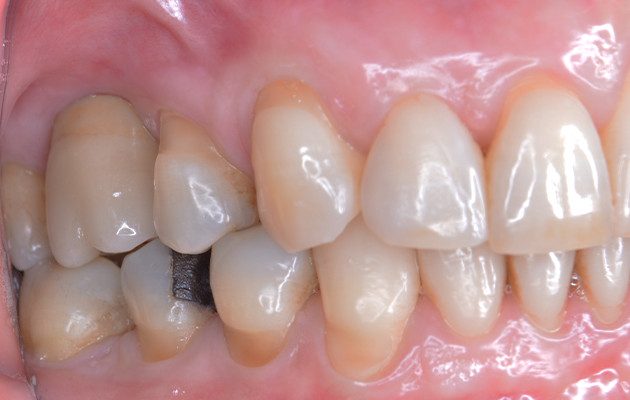

20 | Aspecto final.